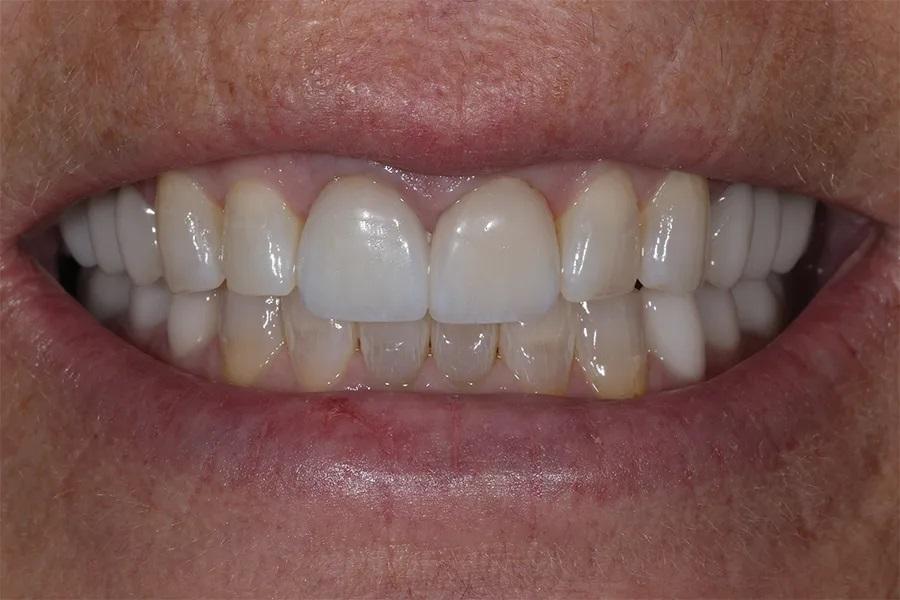

Разделение лечения на этапы в течение 18 месяцев позволило пациентке пройти полную реабилитацию полости рта без значительной одномоментной финансовой нагрузки. Результат превзошел ожидания пациентки, и она была полностью удовлетворена своей новой улыбкой (фото 12–16). При контрольном осмотре через 6 месяцев все реставрации оставались интактными, без сколов и разрушений, при этом пациентка отмечала комфортную окклюзию.

Фото 12. Улыбка анфас после лечения с уменьшенной выраженностью десневой улыбки и более гармоничным обрамлением зубов.

Фото 13. Крупный план улыбки после лечения, демонстрирующий целостность и согласованность реставраций, улучшающих общий вид улыбки.